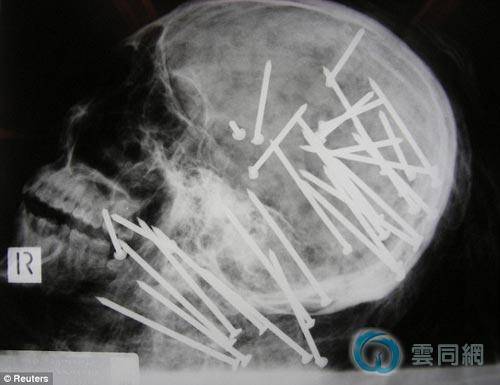

X射线扫描出的影像

澳大利亚悉尼警方昨天公布了一张骇人的被杀华人头骨X光照片,向公众征集破案线索。照片显示被害人头部和颈部共被射入27根长钉。负责侦破的当地警官说,从警36年来从未见过如此残忍的谋杀案件。

警方表示,刘晨死前共身中34根长钉,其中大部分都位于头部和颈部。根据分析,这些长钉都是用一种强力射钉枪从近距离射出的,该枪能够射出最长达85毫米的钉子。警方称,这种不需用电的气动射钉枪广泛地应用于建筑行业,在当地非常容易买到或租到。目前凶器尚未找到。

在警方公布的X光扫描照片中,刘晨的头部和颈部布满多达27根长钉。警方的谋杀侦查负责人贝尔福德说:“我做警察36年了,从未见过如此残忍和恶毒的谋杀手段。”他说,警方决定向公众公布刘晨的头骨照片,是为了展示凶手作案手段的残忍,并向公众征集任何与此案有关的线索,特别是谁在去年10月19日左右曾在案发地带见过刘晨的蓝色陆虎越野车。